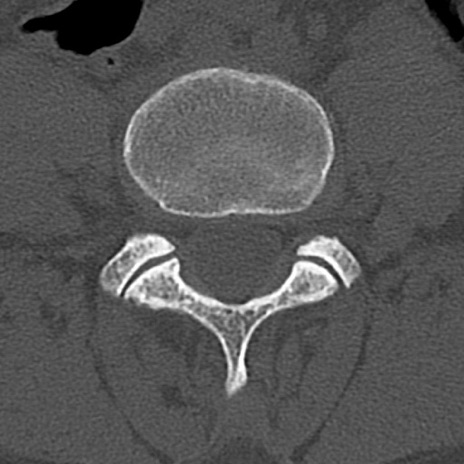

【整形】TIPS症例4 腰椎CT(横断像)

腰椎CT

横断像と矢状断像